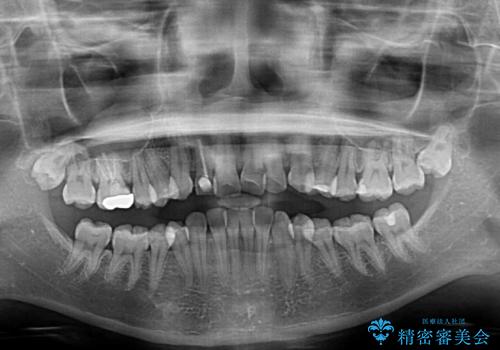

- 前歯の歯並びと不自然な色をした前歯のクラウンを気にして来院された患者様です。

上下前歯の歯列不正はインビザラインにより歯列を整え、その後に、前歯をオーダーメイドタイプのオールセラミッククラウンにて補綴治療することとしました。

前歯のデコボコを一番気にしていらっしゃいましたが、矯正治療により下顎前歯が隠れるほどのディープバイトも一緒に改善され、奥歯に負担のかかりにくい咬み合わせとなりました。